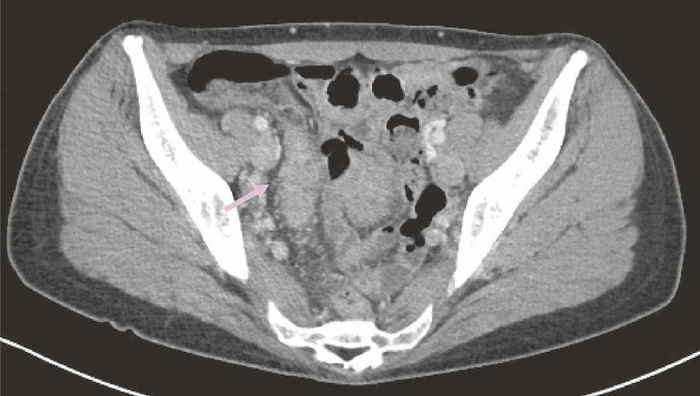

精査で施行したCT,MRIで痔瘻癌が疑われた。

図43 腹部骨盤CT

CTではMRIと同様に広範囲のhigh density areaがあり,癌と炎症が波及した領域の区別がつかず右側方領域にリンパ節腫大を認めた。